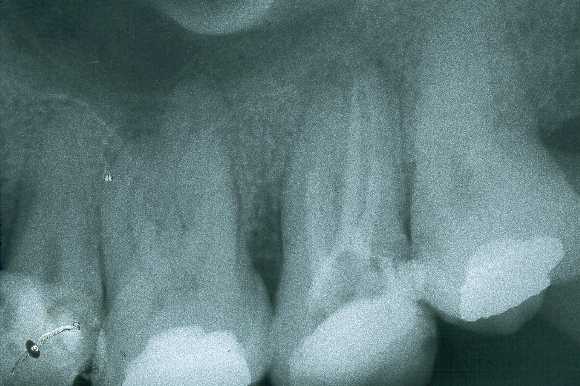

También se detecta dolor a la palpación del fondo de vestíbulo de la zona correspondiente al primer molar superior del mismo lado, refiriendo que se había hecho un tratamiento endodontico recientemente, pero que todavía sentía molestias en el diente.Se observa la radiografía periapical de la zona post-tratamiento endodóntico y se puede observar que dicho tratamiento está terminado de manera defectuosa. La prominencia de la lesión acasionaba el traumatismo por mordedura durante la masticación del paciente.

Se remite al endodoncista para que descarte la posibilidad de infección periapical con diseminación de la infección hacia la vía de drenaje natural del carrillo. El endodoncista devuelve de manera inmediata al paciente diciendo que el tratamiento en cuestión está defectuoso pero que no tiene relación directa con la lesión del carrillo.(fig2)

Radiografía periapical